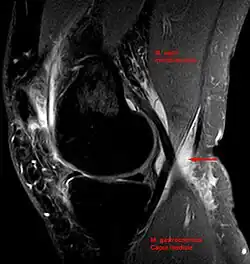

Baker's cyst on MRI, sagittal image

In adults, Baker's cysts usually arise from almost any form of knee arthritis (e.g., rheumatoid arthritis) or cartilage (particularly a meniscus) tear. Baker's cysts in children do not point to underlying joint disease. Baker's cysts arise between the tendons of the medial head of the gastrocnemius and the semimembranosus muscles. They are posterior to the medial femoral condyle.